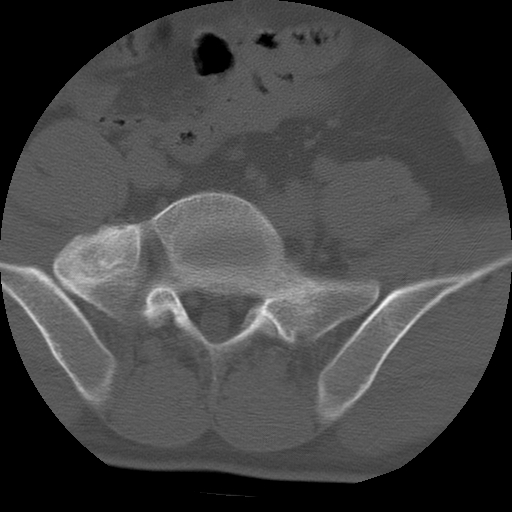

标题: CT24390:男,23岁,腰痛就诊。

男,23岁,腰痛就诊。

腰5右侧横突肥大伴假关节形成.

支持!图像少,再往下扫骶髂关节面,椎小关节毛糙,青年男性需排除as,实验室查b27。

腰5右侧横突肥大伴假关节形成

腰5右侧横突肥大伴假关节形成!支持!

l5右侧横突肥大伴假关节形成。

腰椎骶化或骶椎腰化常见。